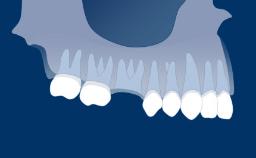

Implant therapy is an elective treatment modality for the rehabilitation of partially and fully edentulous patients.

This module will define risk factors, both systemic and local, in relation to implant therapy as well as relative and absolute contraindications to implant placement.